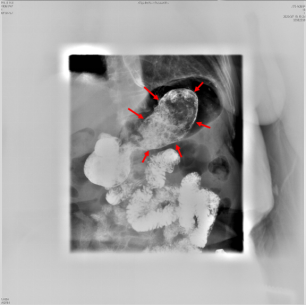

询问病史,患者口服雪碧7日,超声科张华斌主任特意嘱其改为饮用可乐。3日后患者腹痛症状较前明显好转,复查超声,胃结石神奇的消失了。

所见如下:

5,6  胃腔内未见结石